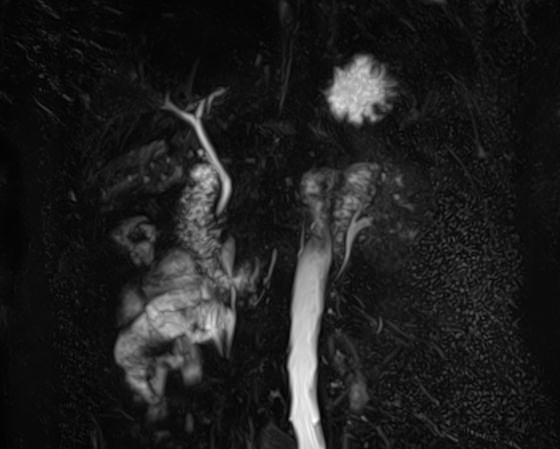

Магнитно-резонансная холангиография – это неинвазивный и безопасный метод исследования, который используется для визуализации желчевыводящих путей, включая внутри- и внепеченочные желчные протоки, панкреатический (Вирсунгов) проток и общий желчный проток (холедох). МРТ позволяет оценить анатомические особенности билиарной системы и определить патологию расположенных рядом структур.

В клинике «Доступная медицина» МР-холангиография выполняется на современном высокопольном томографе закрытого типа TOSHIBA VANTAGE TITAN 1,5 Тесла. Путем послойного сканирования и построения объемных изображений с высокой четкостью и детализацией, аппарат позволяет диагностировать причины возникновения закупорки желчных протоков.

Метод МР-холангиографии имеет высокую информативность и может назначаться перед проведением классической ЭРХПГ (эндоскопической ретроградной холангиопанкреатографии). Преимуществами МР-холангиографии является неинвазивность, отсутствие вредного рентгеновского излучения. Кроме того, исследование не сопряжено с риском развития таких осложнений как острый панкреатит, холангит и др. При этом МР-холангиография имеет важное значение, так как может использоваться как альтернатива ЭРХПГ, если к последней имеются противопоказания, например, аллергические реакции на йодсодержащие контрастные вещества.

С помощью магнитно-резонансной холангиографии можно выявить следующие патологии:

- Закупорка протоков конкрементами;

- Доброкачественные и злокачественные опухоли внутри просвета протоков или новообразования, исходящие из окружающих тканей;

- Рубцовые деформации, спайки, стриктуры желчевыводящих путей.

- Аномалии развития желчевыводящей системы.